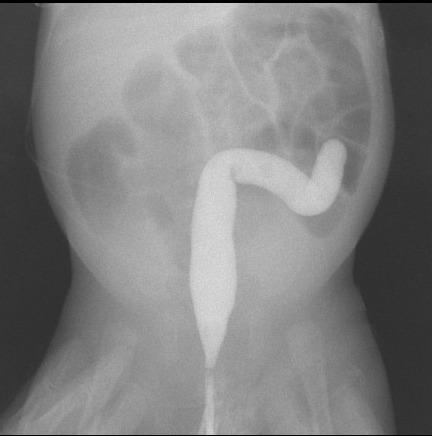

À l’examen clinique, vous notez : fréquence cardiaque 140/min ; fréquence respiratoire 45/min ; saturation pulsée en oxygène (SpO2) 94 % à la main droite, 88 % à la main gauche ; pouls radiaux et fémoraux perçus. Auscultation cardiaque normale. Murmure vésiculaire bilatéral et symétrique. Abdomen souple.